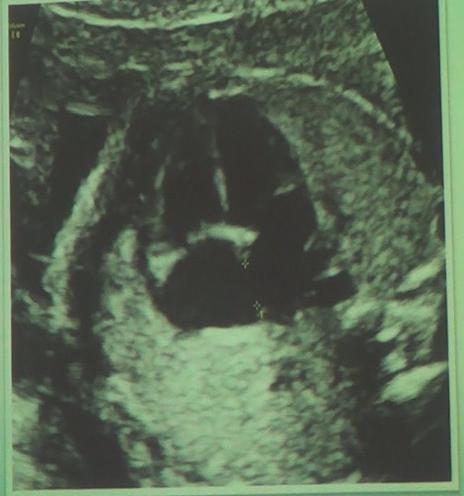

单心室 主动脉弓缩短

主动脉弓离断 脐静脉腹内段瘤样扩张